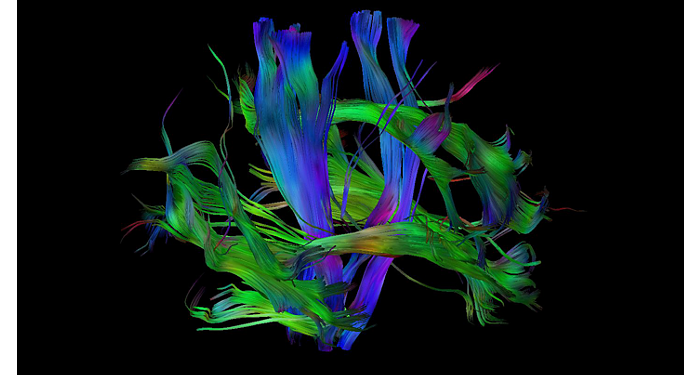

El 70% de los radiólogos consideran que las indicaciones neurológicas son un desafío, sobre todo debido a la falta de técnicas apropiadas de imagenología y visualización¹. Philips tiene como objetivo proporcionar la mejor claridad de diagnóstico posible y orientación terapéutica para todos los pacientes con trastornos neurológicos. Al aprovechar nuestra plataforma digital dStream, este año presentamos un conjunto de estrategias nuevas de imagenología y visualización. Esto puede ayudarlo a resolver preguntas sobre neurología complejas con mayor certeza, así como a desbloquear nuevos territorios neurológicos en aplicaciones neurofuncionales avanzadas. Este es un paso clave para aumentar el diagnóstico neurológico y, en última instancia, impactar más vidas con la RM. ¹ TMTG Market Survey 2016

Nuevas aplicaciones neurológicas

En Philips, creamos innovaciones de IRM que son importantes para personas reales: los radiólogos encargados de hacer más, mejor y más rápido, los médicos que requieren resultados confiables para hacer diagnósticos confiables, los investigadores que buscan respuestas a preguntas consecuentes y los pacientes que anhelan una experiencia más sencilla y respuestas directas.